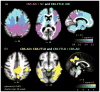

Results: CBD was associated with 4 clinical syndromes: progressive nonfluent aphasia (n = 5), behavioral variant frontotemporal dementia (n = 5), executive-motor (n = 7), and posterior cortical atrophy (n = 1). Behavioral or cognitive problems were the initial symptoms in 15 of 18 patients; less than half exhibited early motor findings. Compared to controls, CBD patients showed atrophy in dorsal prefrontal and perirolandic cortex, striatum, and brainstem (p < 0.001 uncorrected). The most common pathologic substrates for clinical CBS were CBD (35%), Alzheimer disease (AD, 23%), progressive supranuclear palsy (13%), and frontotemporal lobar degeneration (FTLD) with TDP inclusions (13%). CBS was associated with perirolandic atrophy irrespective of underlying pathology. In CBS due to FTLD (tau or TDP), atrophy extended into prefrontal cortex, striatum, and brainstem, whereas in CBS due to AD, atrophy extended into temporoparietal cortex and precuneus (p < 0.001 uncorrected).